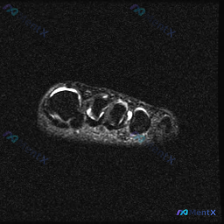

踝关节MRI看到软组织积液,我整理了完整分析思路

最近遇到这份踝关节MRI读片,看到报告提了软组织积液,整理了完整分析思路分享给大家。

这是踝关节MRI T2序列矢状位图像,核心发现整理如下:

- 骨骼结构:胫骨远端、距骨、跟骨皮质完整,无明确骨折线,无明显弥漫性骨髓水肿高信号

- 关节结构:胫距关节软骨平整,关节液信号正常;距下关节腔内可见显著异常高信号液体积聚;跗骨窦区域存在明显软组织信号异常,大量高信号液体聚集/水肿

- 软组织与韧带:距腓前韧带(ATFL)区域可见明显组织水肿,局部结构连续性欠佳,伴周围软组织水肿;跟腱走行连续,信号均匀,无撕裂或炎症表现;足底腱膜结构基本完整

- 无明显骨侵蚀、骨破坏表现